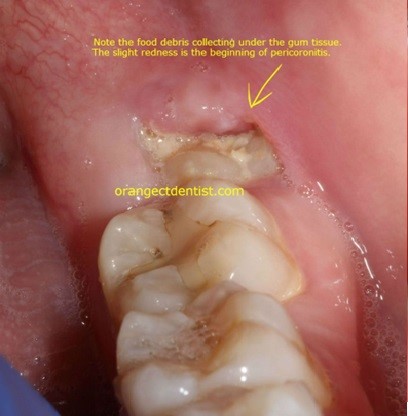

Operculectomy is a minor surgical procedure involving the removal of the operculum, a flap of gum tissue that covers a partially erupted tooth, most commonly a wisdom tooth (third molar). This procedure is often performed to alleviate pain, reduce the risk of infection, and resolve issues caused by food and bacteria trapped under the gum flap.

Pericoronitis: Inflammation and infection of the gum tissue surrounding a partially erupted tooth.